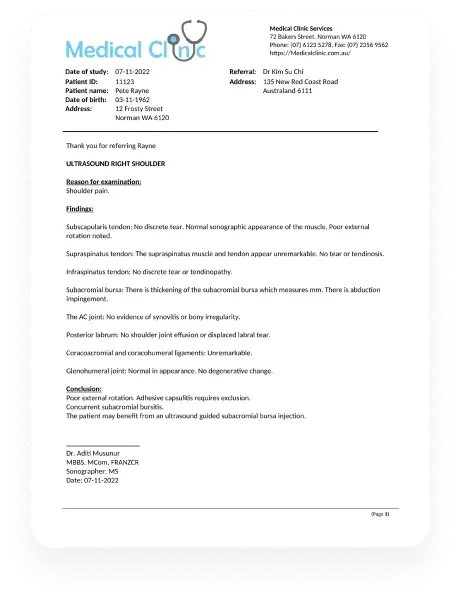

Report viewing

Enable referrers or specialists to access patient reports directly, eliminating the need for additional communication with your clinic.

Document accessibility

Provide a platform for sharing supplementary documents like growth charts or blood reports, making them readily available on the portal.